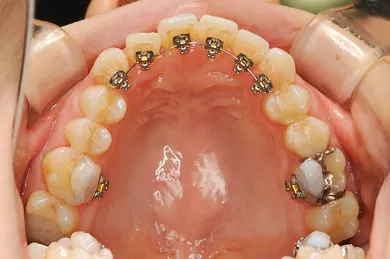

特徴2「目立たない」装置も/「裏側」の部分矯正も対応

歯の表側に付けるワイヤー矯正の他、歯の裏側に付ける裏側部分矯正、透明なマウスピース矯正(インビザライン)等、患者さんの好みの装置を選択できます。装置によって費用は異なりますのでご相談ください。

「裏側」ワイヤー矯正

歯の裏側に矯正装置を付けます。

部分矯正を歯の裏側から行う医院は多くないので、

興味のある方は是非お問い合わせください。